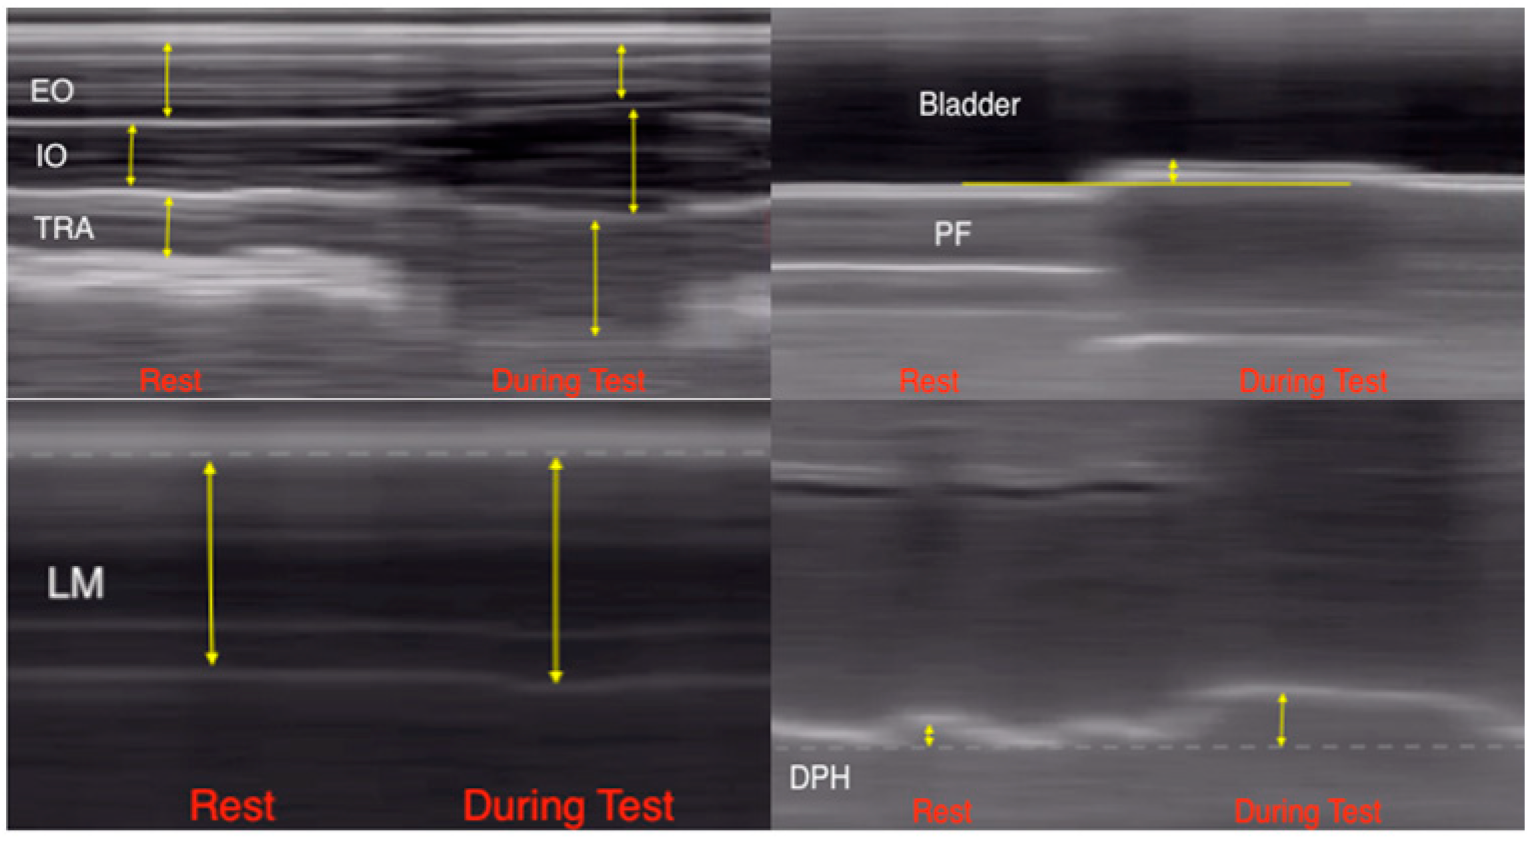

| Muscle | Probe | Transducer Placement | Transducer Bandwidth | Caliper Placing |

|---|---|---|---|---|

| DPH [27] | Convex | Right anterior axillary line, subcostal. The gallbladder and inferior vena cava were taken as anatomical landmarks. | 2.5–3.5 MHz | Distance (mm) from the most distal apex of the right hemi diaphragm to the midpoint of the convex probe coinciding with the hyperechogenic curved line of the diaphragm dome. |

| PF [32] | Convex | Suprapubic, in the mid-sagittal and transabdominal plane. The probe was tilted caudally and posteriorly to obtain a clear image of the postero-inferior aspect (base) of the bladder, which varied depending on the bladder fullness of the participants. | 2–5 MHz | The limit located between the hypoechoic region that represents the full bladder and the hyperechoic region that corresponds to the PF musculature. |

| LAW [33] | Linear | The right abdominal wall at the midpoint between the lower angle of the thoracic cage and the iliac crest. The medial edge of the transducer was placed approximately 10 mm from the alba linear. | 7.5 MHz | Distance (mm) between the superficial and deep border of each muscle belly, which is marked by the hyperechoic fascial lines. The fascial lines were not included in the measurement. |

| LM [34] | Linear | L4–L5 facet joint over the articular pillar and the belly of the L4–L5 muscle over the articular pillar and the belly of the ML muscle. | 5 MHz | Distance (mm) from the most posterior portion of the zygapophyseal joint of L4–L5 and the muscle surface separating it from the subcutaneous cellular tissue. |